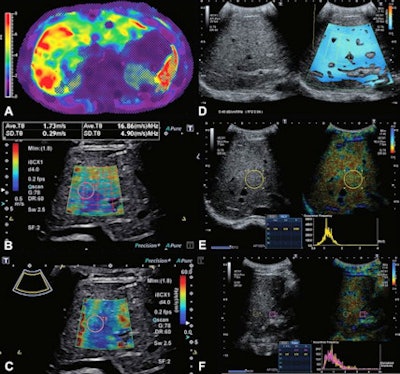

Images show MR elastography and quantitative ultrasound images in 16-year-old boy with Fontan-associated liver disease and elevated liver shear stiffness (5.4 kPa with gradient-recalled echo MR elastography). (A) Axial MR elastogram with 95% confidence map overlay shows a stiff (5.4 kPa) heterogeneous liver. Image colors indicate stiffness (in kPa) according to the scale left of the elastogram image. (B) A transverse 2D shear-wave elastography ultrasound image with shear-wave speed of 1.73 m/sec (9 kPa). (C) A transverse shear-wave dispersion map with dispersion of 16.86 m/sec/kHz. (D) A split-screen transverse image shows a liver attenuation measurement of 0.46 dB/cm/MHz. (E) A split-screen transverse image shows a normalized local variance measurement of 1.24. (F) A split-screen longitudinal image shows a hepatorenal index measurement of 1.07. Images courtesy of RSNA.MRI scans were performed on a 1.5-tesla scanner (Ingenia, Philips). Ultrasound scans were performed immediately afterward (Aplio i800, Canon Medical Systems USA). The team found that ultrasound shear-wave speed and MR elastography-derived stiffness had a positive correlation of 0.73 (p = 0.001).

Shear-wave speed also had an area under the receiving operating curve (AUC) of 0.95 for predicting abnormal liver stiffness with MR elastography. The researchers added that ultrasonic attenuation had an AUC of 0.75 for predicting abnormal liver MRI proton density fat fraction.